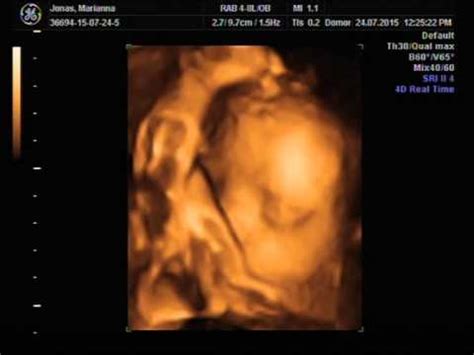

A 29 hetes terhesség a nyolcadik hónap, a harmadik trimeszter kezdete. Ez a várandósság utolsó és leghosszabb szakasza. A 29 hetes magzat a héten már közel 37 cm hosszú, súlya pedig 1,25 kg körüli, és gyorsan növekszik. Tulajdonképpen a terhesség utolsó két és fél hónapjában szerzi meg születési súlyának körülbelül felét.

A magzat tovább növeszti izmait, fejlődik a tüdeje és az agya, ezzel egyidőben a kis feje is, valamint elkezdi szabályozni a saját testhőmérsékletét. Az ultrahang vizsgálat alapján mért magzati méretek a terhesség 29. hetében: BPD (fejátmérő): 75 (+/- 4,0) mm, HC (fej körfogat): 269 (+/- 25) mm, AC (has körfogat): 259 (+/- 25) mm, FL (combcsont hossz).

Fontos! A feltüntetett értékek hozzávetőlegesek, átlagértékek, a magzati kor, valamint az egyéni tényezők függvényében eltérőek lehetnek, ami nem jelenti azt, hogy bármilyen probléma lenne, ezzel kapcsolatban minden esetben az orvos a mérvadó. Az értékeket az ausztrál népesség átlag adatai alapján, S Campbell Westerway határozta meg.